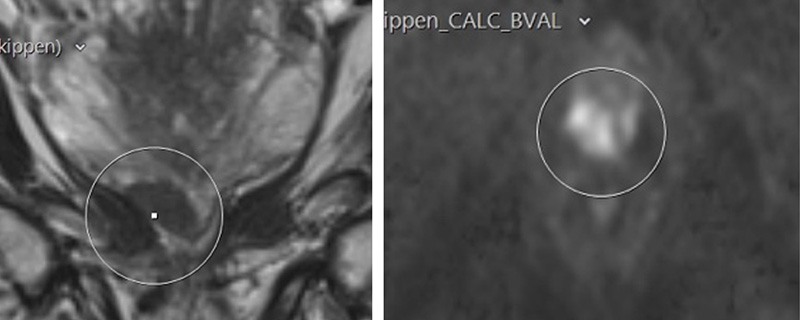

MRT-Kontrolle eines Patienten in aktiver urologischer Überwachung.

Links: anatomisches MRT-Bild in dem der Tumor dunkel und glatt berandet dargestellt ist

Rechts: diffusionsgewichtetes MRT-Bild in dem der kleine Tumor hell dargestellt ist